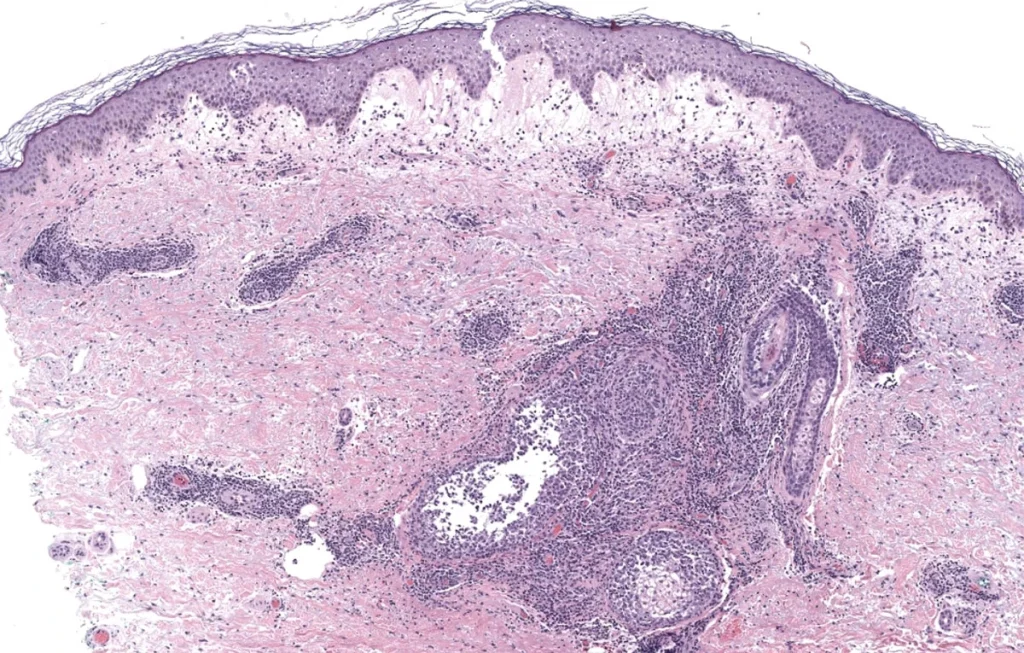

Patrones histológicos dermatopatología

- Módulo 7: Patrón nodular/difuso